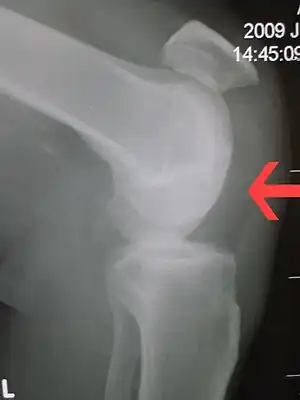

| Patellar tendon rupture showing a great distance between the tibial tuberosity and the bottom of the knee cap. Arrow marks this enlarged space. | |

Patellar tendon rupture can usually be diagnosed by physical examination. The most common signs are: tenderness, the tendon's loss of tone, loss of ability to raise the straight leg and observation of the high-riding patella. Radiographically, patella alta can be detected using the Insall and Salvati method when the patella is shorter than its tendon. Partial tears may be visualized using MRI scans.[4]